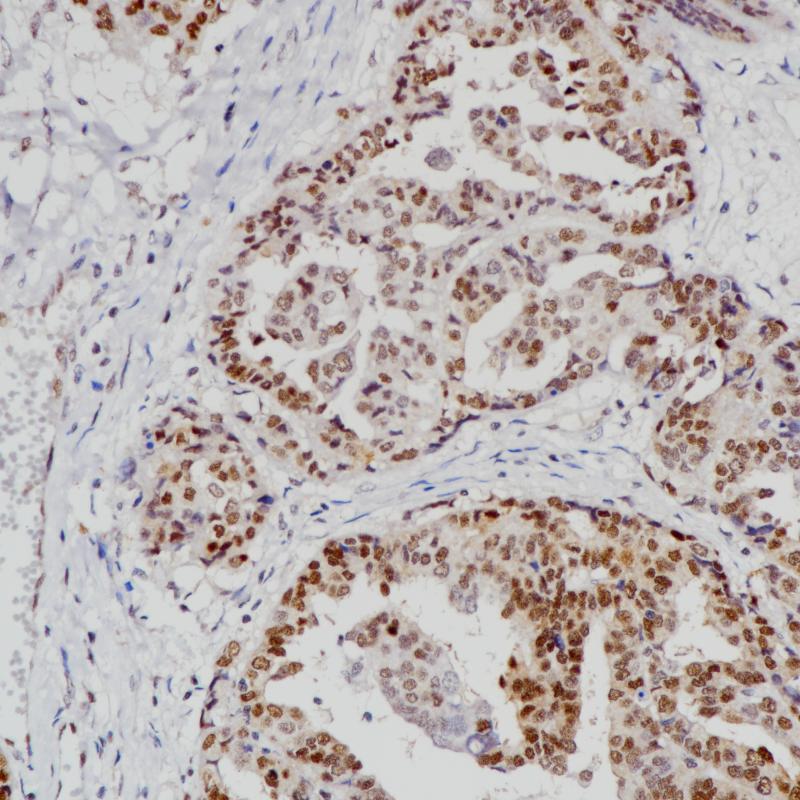

EGFR 重组兔单克隆抗体

阳性对照

肺癌

亚细胞定位

细胞膜/细胞质